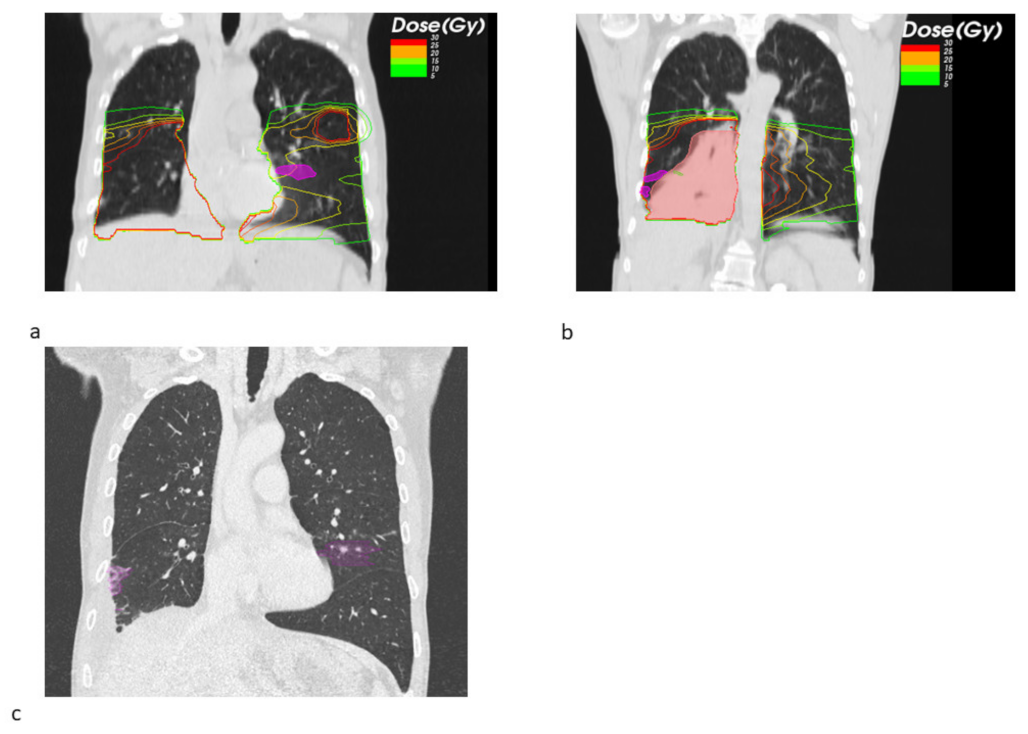

3. Results